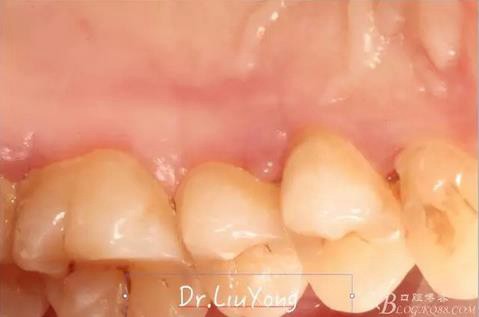

術(shù)后兩周,復(fù)查,A1達(dá)到了完全的根面覆蓋,B1牙齦退縮由原來(lái)的3.5mm減少到1mm,B2近中牙齦也得到部分的恢復(fù),同時(shí)所有牙齦邊緣都通過(guò)手術(shù)增厚。如上圖

A區(qū)結(jié)締組織取瓣區(qū)域的愈合后照片,如上圖